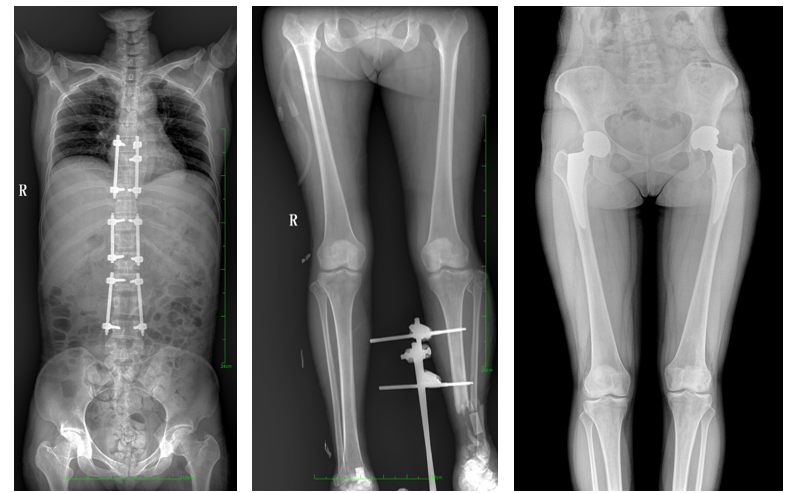

17"*34"有效視野,是市面大尺寸平板的2倍,一次成像不拼接。相較于多張攝影再軟件拼接的DR設備,PLX8600解決了拼接圖像存在密度不均勻,拼接處圖像配準和放大效應等問題,給臨床帶來了真正的大視野影像解決方案,高清畫質,準確成像不失真,可一次性覆蓋全脊柱或雙下肢影像。PLX8600大視野平板動態DR攝影速度快,患者可以更快的完成檢查,且單次攝影輻射劑量是常規多張攝影再軟件拼接DR的1/2或1/3,低劑量給患者更多關愛。

除常規靜態攝影外,PLX8600大平板具備動態透視和點片功能,透視采集功能可支持大視野、多角度的可視化觀察。通過可視化的動態影像,配合點片功能,能夠很好的觀察復雜部位病灶,有效的抓取關鍵幀,降低患者多次攝片的概率,安全又高效。如:全脊柱狀態評估、長骨關節活動度、下肢靜脈造影瓣膜功能評估、消化道功能評估、脊髓造影等更多大視野臨床應用,多面手給醫生更多驚喜。